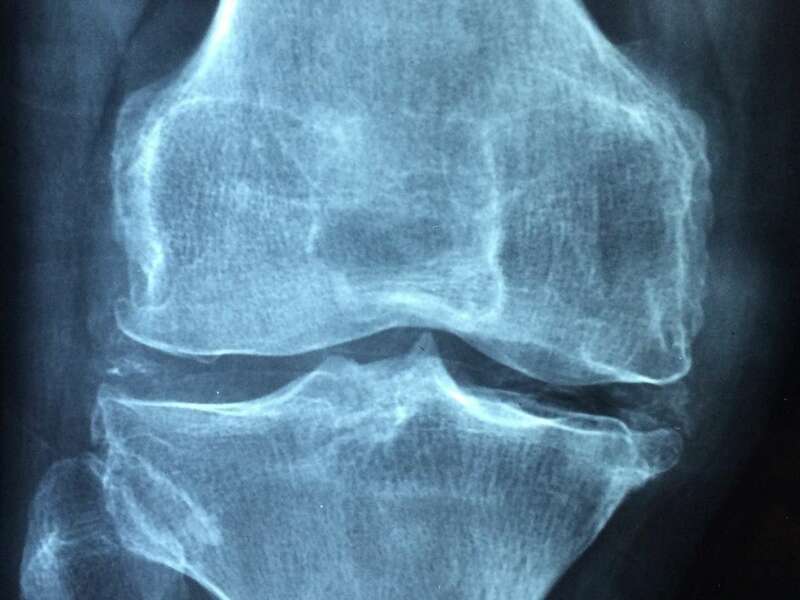

L’arthrose est un véritable problème de santé publique de nos jours. Elle représente l’une des principales causes de perte d’autonomie chez les personnes âgées. On estime qu’environ 65% des sujets de plus de 65 ans souffrirait d’arthrose. La gonarthrose concerne 30% des personnes de 65 à 75 ans. L’atteinte fémoro-tibiale interne est la plus fréquente et peut être due à une déviation de l’axe mécanique. L’atteinte fémoro-patellaire concerne plus souvent les sujets jeunes faisant suite à un traumatisme endommageant le cartilage ou à une instabilité de la rotule.

L’arthrose désigne un processus d’usure du cartilage liée au vieillissement. Ce n’est pas une fatalité liée à l’âge. Elle cause des dommages irréversibles du cartilage qui perd au fur et à mesure son rôle de surface de glissement et d’amortisseur. La pression sur l’os s’accroît à mesure que l’épaisseur cartilagineuse diminue.

Des excroissances osseuses, appelées ostéophytes, des kystes osseux et des ulcérations cartilagineuses se forment progressivement. En réponse, la membrane synoviale devient inflammatoire et produit un liquide synovial. L’excès de pression articulaire et l’inflammation sont les causent des douleurs de genou. La perte de congruence de l’articulation entraîne quant à elle, une diminution de la mobilité articulaire.

L’arthrose n’entraine pas toujours des douleurs. On parle de dissociation radio-clinique : une arthrose visible radiologiquement n’est pas forcément responsable de douleurs. Dans ce cas, aucun traitement n’est nécessaire.

Elle sera confirmée par des examens radiologiques tels que des radiographies du genou. En cas de doute diagnostic ou afin de rechercher d’éventuelles lésions associées, un scanner et/ou une IRM pourront être prescrits.